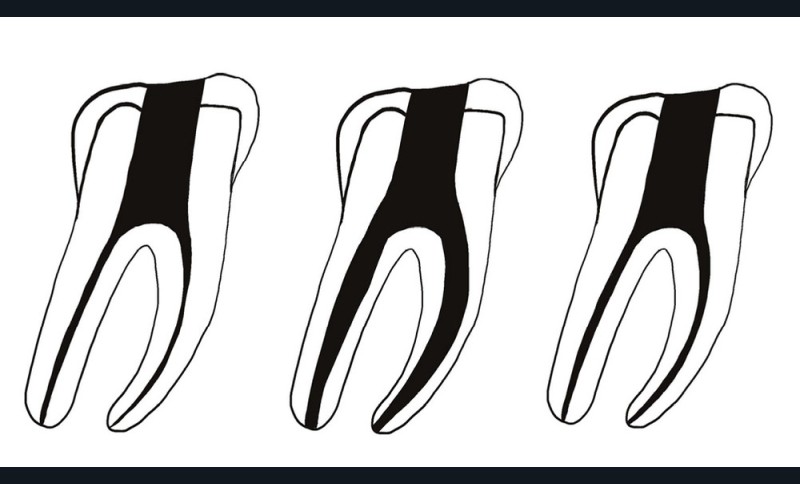

La préparation canalaire

L’anatomie canalaire est bien plus complexe que ce qu’il est possible de visualiser cliniquement et radiographiquement [8]. De plus, les canaux principaux ont eux-mêmes une anatomie qui n’est pas ronde mais ovalaire dans la plupart des cas. Elle peut également être de forme conique, pyramidale, en ruban (ou aplatie), en huit, en C, trapézoïdale, en goutte d’eau, etc. [9]. Ces différents schémas anatomiques ne concordent pas avec la forme ronde des préparations réalisées par la majorité de l’instrumentation canalaire disponible (fig. 6). Cela a pour conséquences des surfaces canalaires non touchées (pouvant aller jusqu’à 55 %), des débris non nettoyés [10] pouvant être responsables d’infections secondaires [11].